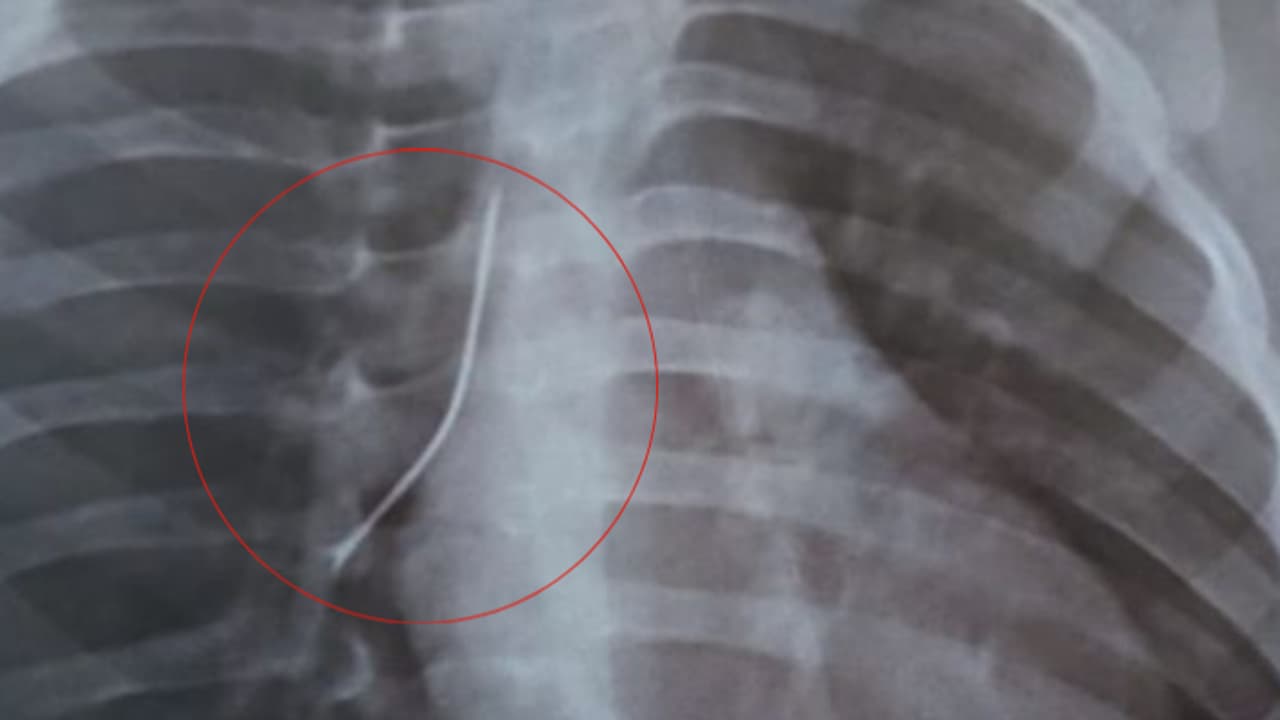

കൊച്ചി: ഒരു വയസ് മാത്രം പ്രായമുള്ള കുഞ്ഞിന്റെ ശ്വാസനാളത്തിൽ നിന്ന് 4 സെന്റീമീറ്റർ നീളമുള്ള സേഫ്റ്റി പിൻ പുറത്തെടുത്തു. എറണാകുളം വിപിഎസ് ലേക്ഷോർ ആശുപത്രിയിൽ നടത്തിയ ബ്രോങ്കോസ്കോപിയിലൂടെയാണ് പിൻ പുറത്തെടുത്തത്. ശ്വാസമെടുക്കാൻ കടുത്ത ബുദ്ധിമുട്ട് അനുഭവപ്പെട്ടതിനെ തുടർന്ന് അത്യാഹിത വിഭാഗത്തിലെത്തിച്ച കുട്ടിയുടെ ശ്വാസനാളത്തിൽ എക്സേറേ പരിശോധനയിലാണ് പിൻ കണ്ടെത്തിയത്.

അതീവ അപകട സാധ്യത കണക്കിലെടുത്ത് അടിയന്തിരമായി ബ്രോങ്കോസ്കോപ്പിക്ക് കുട്ടിയെ വിധേയമാക്കി. വിപിഎസ് ലേക്ഷോറിലെ പൾമണറി ക്രിട്ടിക്കൽ കെയർ & സ്ലീപ്പ് മെഡിസിൻ വകുപ്പിലെ കൺസൾട്ടന്റായ ഡോ. മുജീബ് റഹ്മാന്റെ നേതൃത്വത്തിലാണ് ബ്രോങ്കോസ്കോപി നടത്തിയത്. കുട്ടി ഇപ്പോൾ സുഖം പ്രാപിക്കുന്നതായാണ് ആശുപത്രി അധികൃതർ അറിയിക്കുന്നത്.